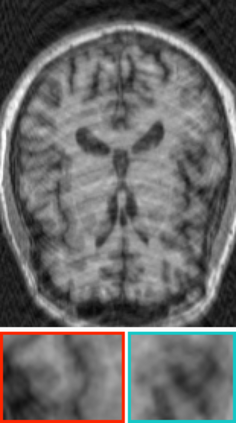

Deep neural networks for medical image reconstruction are traditionally trained using high-quality ground-truth images as training targets. Recent work onNoise2Noise (N2N) has shown the potential of using multiple noisy measurements of the same object as an alternative to having a ground truth. However, existing N2N-based methods cannot exploit information from various motion states, limiting their ability to learn on moving objects. This paper addresses this issue by proposing a novel motion-compensated deep image reconstruction (MoDIR) method that can use information from several unregistered and noisy measurements for training. MoDIR deals with object motion by including a deep registration module jointly trained with the deep reconstruction network without any ground-truth supervision. We validate MoDIR on both simulated and experimentally collected magnetic resonance imaging (MRI) data and show that it significantly improves imaging quality.

翻译:用于医学图像重建的深神经网络传统上是用高质量的地面真实图像作为培训目标来培训的。最近关于噪音2噪声(N2N)的工作表明,有可能使用同一物体的多重噪音测量来替代地面真相;然而,现有的N2N方法不能利用来自各种运动状态的信息,限制了它们了解移动物体的能力。本文件通过提出一个新的运动补偿深度图像重建(MoDIR)方法来解决这一问题,该方法可以使用来自若干未登记和吵闹的测量数据的信息进行培训。MDIR处理物体运动问题的方式是,在没有地面真相监督的情况下,与深层重建网络共同培训一个深层登记模块。我们在模拟和实验收集的磁共振成像(MRI)数据上验证了MDIR,并表明它大大提高了成像质量。